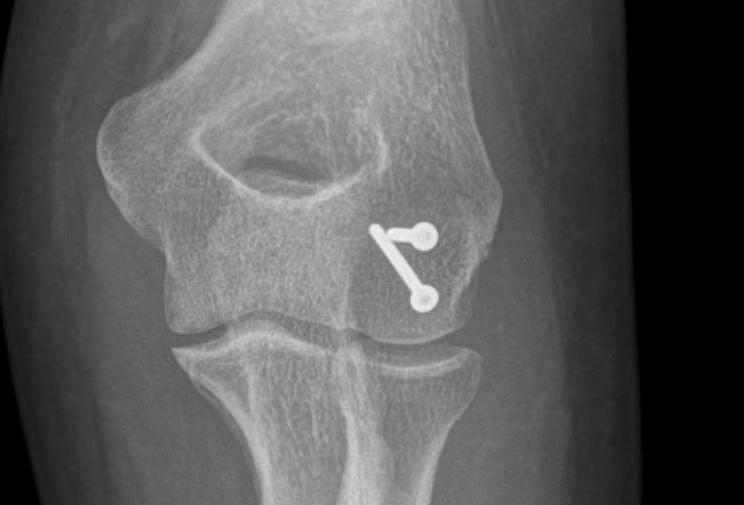

ORIF with AP screws

ORIF Type II with screws

Headless compression screws AP / PA

Posterolateral plate

Usually AP headless compression screws (violates articular surface)

- +/- PA screws (risk AVN)

- +/- excise isolated cartilage lesions

- +/- postero-lateral plate